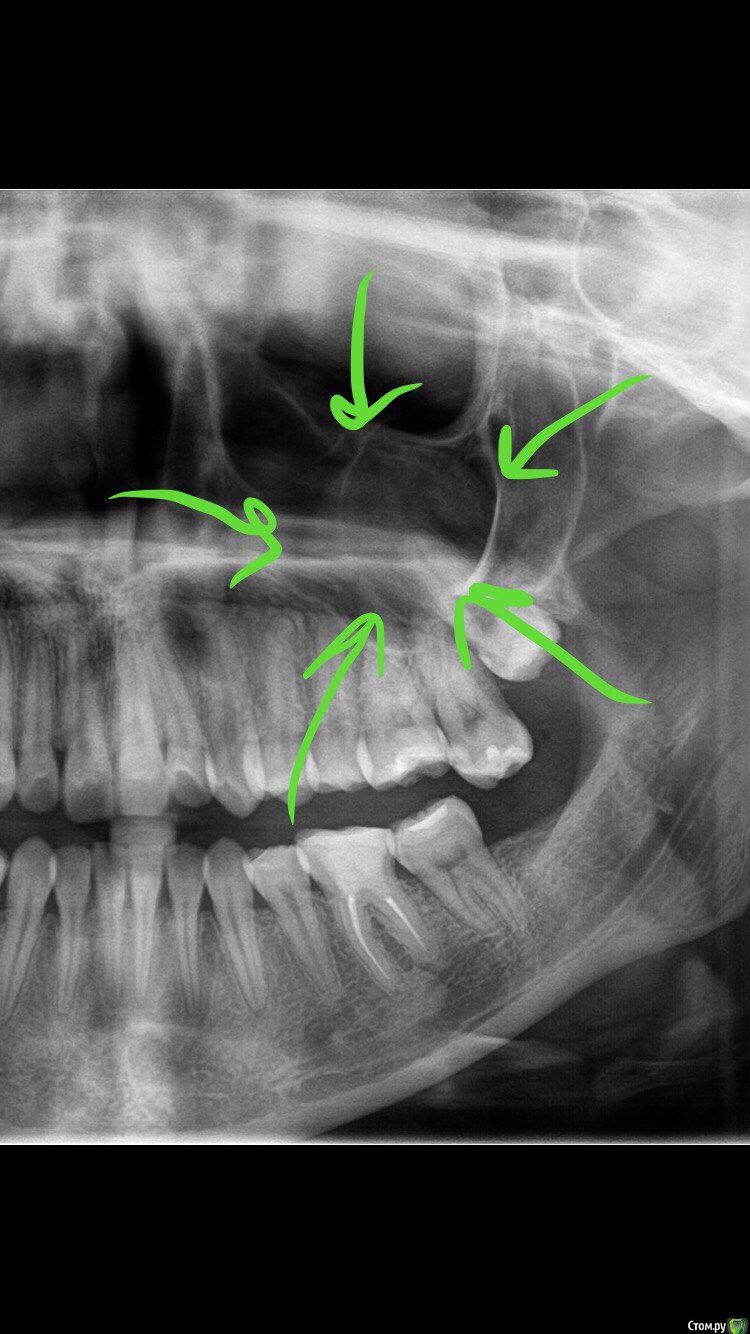

3) Через несколько месяцев после пломбировки к/к боль усилилась, я сделала дентальную КТ, на которой была обнаружена киста гайморовой пазухи и небольшое разряжение у корней зуб (также оказалось, что на по ОПТГ, сделанной перед самой пломбировкой к/к киста была уже в пазухе, но стоматолог не увидел ее на снимке).

Киста на ОПТГ

post-50922-0-18250400-1517780019_thumb.jpg